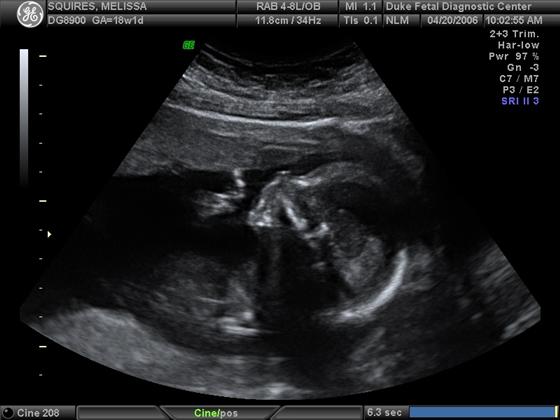

Pics from the 18 week sono...

He doesn't look as much of a skeleton that I thought he would!

1st pic profile pic of him yawning, 2nd pic is him in all of his glory, and the 3D pic. What do you think? Thanks! Image Attachment(s):